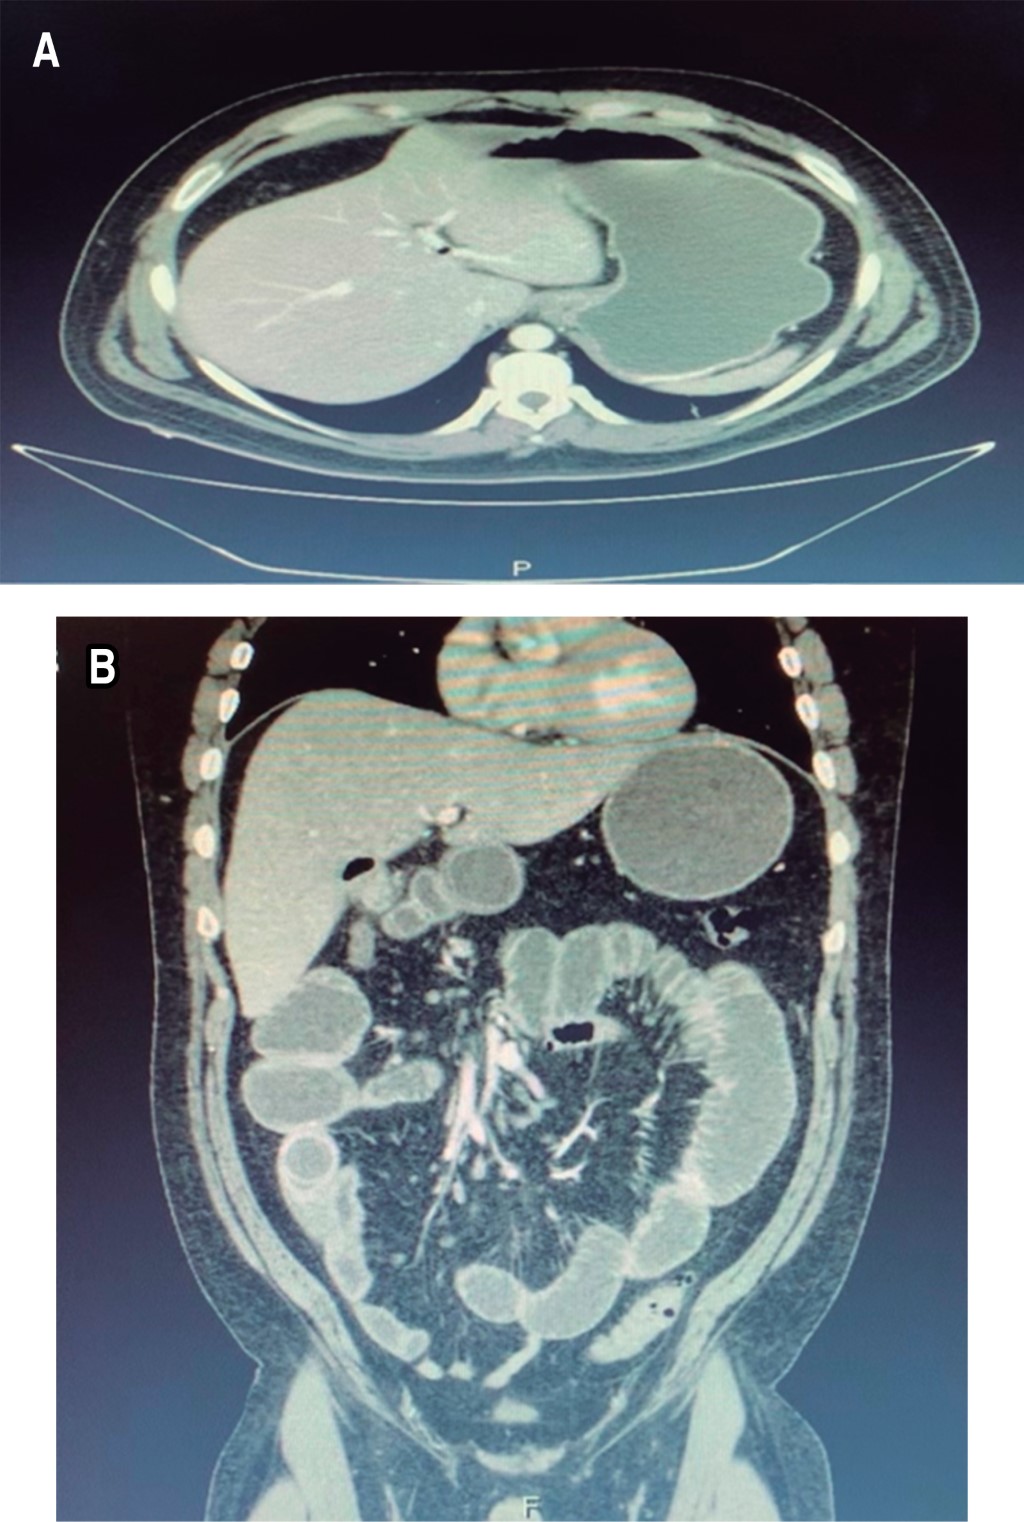

On standing and decubitus abdominal simple radiographs (Figure 1) a coin stack image was evidenced, as well as distension of the small bowel loops, with the absence of gas in the distal intestine.

The imaging studies began with abdominal radiographs in which Rigler's triad was expected to be evidenced: ectopic gallstone, pneumobilia, and distension of intestinal loops; the diagnosis is considered when two of these are present, and we speak of Rigler's tetrad when the change of position of the stone concerning the previous radiograph is documented.1,2 In our patient, it was impossible to find these findings since the simple abdominal X-rays only showed a hydro-aerial level in the right hemiabdomen, distension of intestinal loops, and absence of air in the distal intestine.

Chang and colleagues, in 2018, reported that Rigler's triad on radiographs is present in 14 to 53% of cases, whose sensitivity is 40 to 70%, as well as the visualization of gallstones in 10 to 20% of cases in those containing calcium to be radio opaque.2,6 This was also according to what was found in our patient. For that reason, a cholesterol stone was thought to be present, and since there was no apparent cause of the obstruction, a contrasted abdominal tomography scan was requested, which is currently considered the study of choice for diagnosis since it is possible to visualize Rigler's triad in up to 80% of cases with an approximately 90% sensitivity.1,6

Figure 1